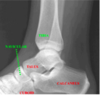

1

Tibia

2

Navicular

3

Talus

4

Calcaneus

5

Cuboid